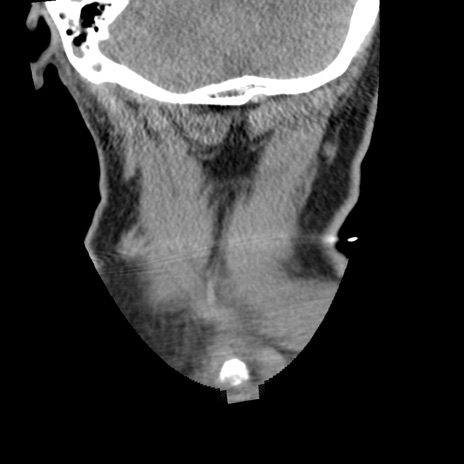

症例50 頚椎CT(冠状断像)

【症例】60歳代女性

【主訴】後頭部〜右後頸部にかけての痛み

【現病歴】本日飲食店でコーヒーを飲んでいたところ、突然後頭部〜右後頸部にかけて痛みが出現し、右上肢の感覚障害を伴ったため救急要請。

【身体所見】脳神経学的に明らかな異常所見を認めず。右上肢に軽度の感覚障害あり。

異常所見と診断は?

頚椎CT